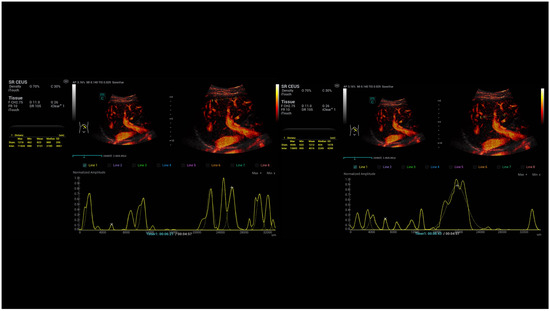

- Kaiser, U.; Vehling-Kaiser, U.; Kück, F.; Gilanschah, M.; Jung, F.; Jung, E.M. Super-Resolution contrast-enhanced ultrasound examination down to the microvasculature enables quantitative analysis of liver lesions: First Results. Life 2025, 15, 991. [Google Scholar] [CrossRef]

- Jung, E.M.; Ocaña Moran, V.; Engel, M.; Krüger-Genge, A.; Stroszczynski, C.; Jung, F. Modified contrast-enhanced ultrasonography with the new high-resolution examination technique of high frame rate contrast-enhanced ultrasound (HiFR-CEUS) for characterization of liver lesions: First results. Clin. Hemorheol. Microcirc. 2023, 83, 31–46. [Google Scholar] [CrossRef] [PubMed]